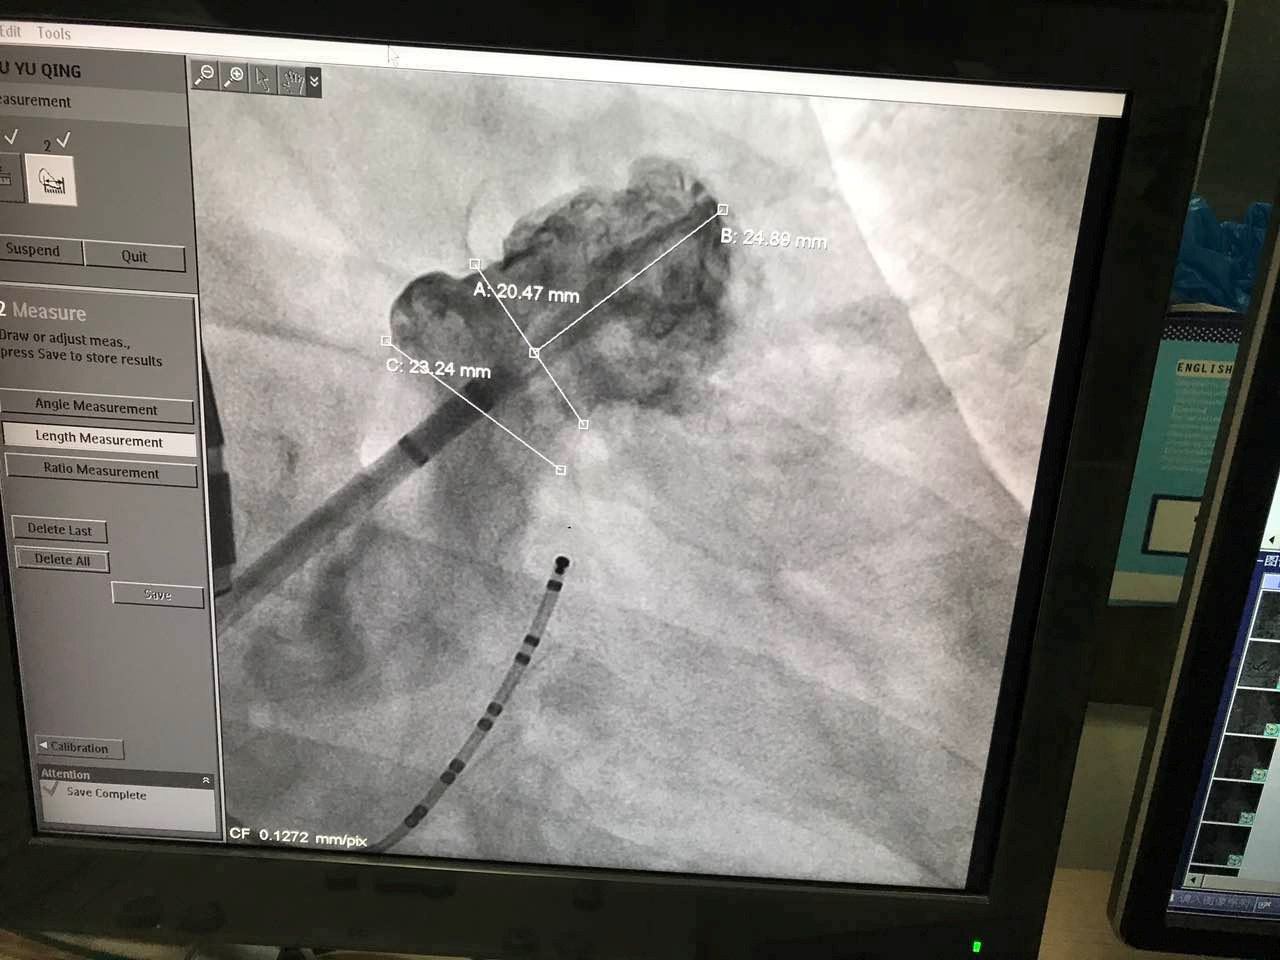

7月3日11点10分,第二例使用LAmbre?左心耳封堵器进行的封堵手术顺利进行。该患者为61岁男性,术中丈量患者左心耳开口为21mm,左心耳深度为25mm。本例手术选用型号为2632的LAmbre?左心耳封堵器;坪字魅魏土忠菹鸵缴锪仆哦泳康囊绞豕餐訪Ambre?左心耳封堵器卓越的设计和卓越的术中机能,不到半幼时便实现对病人左心耳的齐全封堵。本例手术的重要术者之一,在国际上占有多年左心耳封堵手术经验的林逸贤医生于术后暗示:“相较于其它同类产品,LAmbre?左心耳封堵器极大的简化了手术过程,缩短了手术功夫。”

图:术中造影